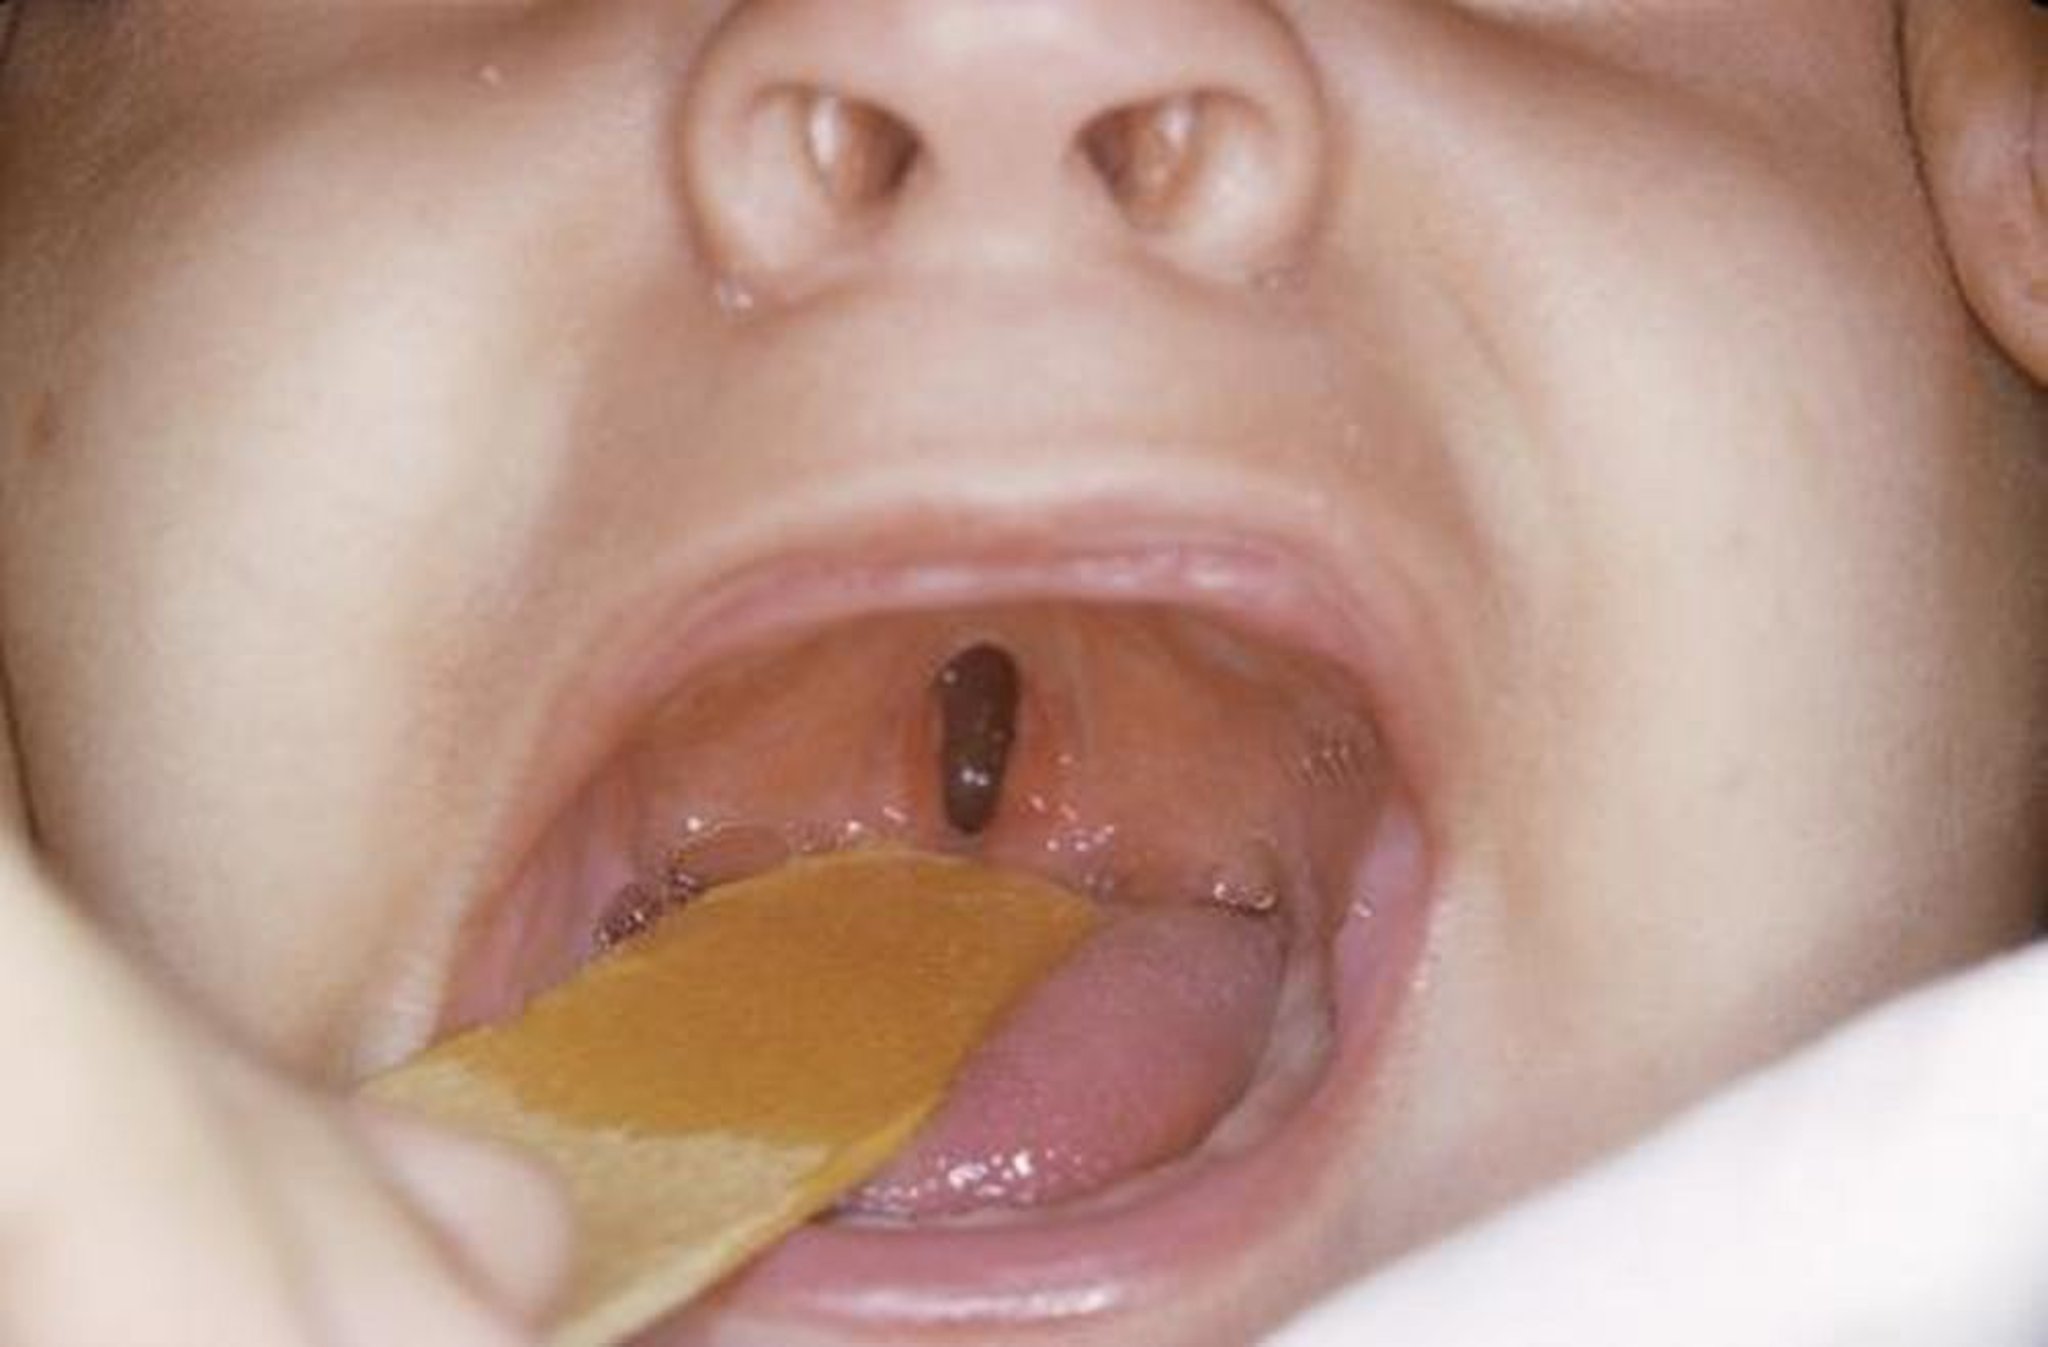

Fente palatine

MORRIS HUBERLAND/SCIENCE PHOTO LIBRARY